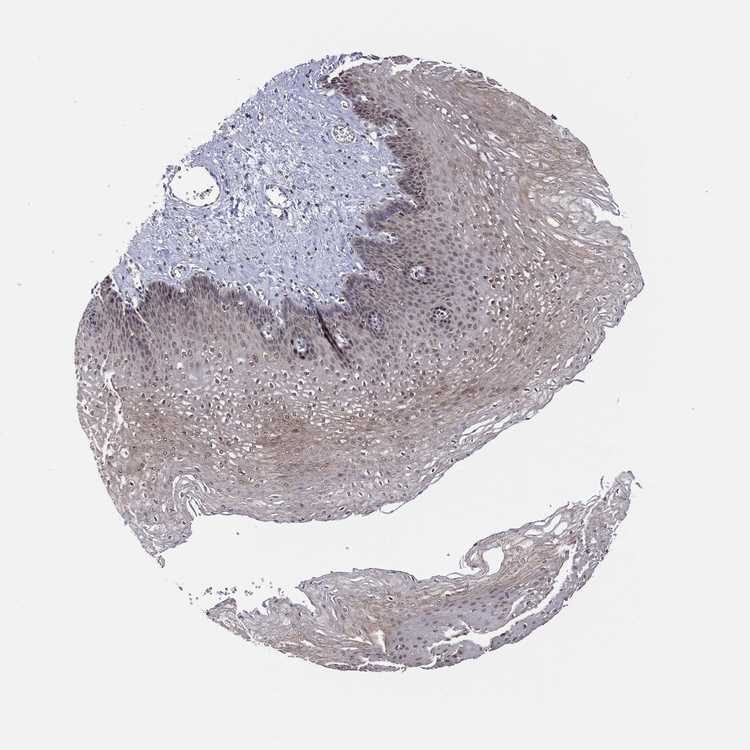

ESOPHAGUS - Antibody stainingi

Antibody staining in the annotated cell types in the current human tissue is reported as not detected, low, medium, or high, based on conventional immunohistochemistry profiling in selected tissues. This score is based on the combination of the staining intensity and fraction of stained cells.

Each image is clickable and will lead to virtual microscopy that enables deeper exploration of all samples and also displays staining intensity scores, fraction scores and subcellular localization as well as patient and tissue information for each sample.

Antibody HPA066948Antibody CAB012647

Squamous epithelial cells Not detectedMedium